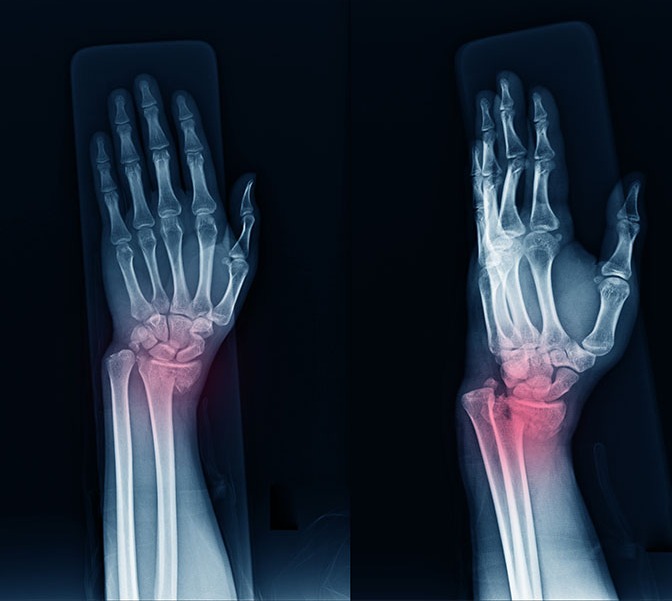

Bone Trauma Consultation

Specialized management of complex fractures and orthopaedic emergencies of the hand, wrist, and upper limb.